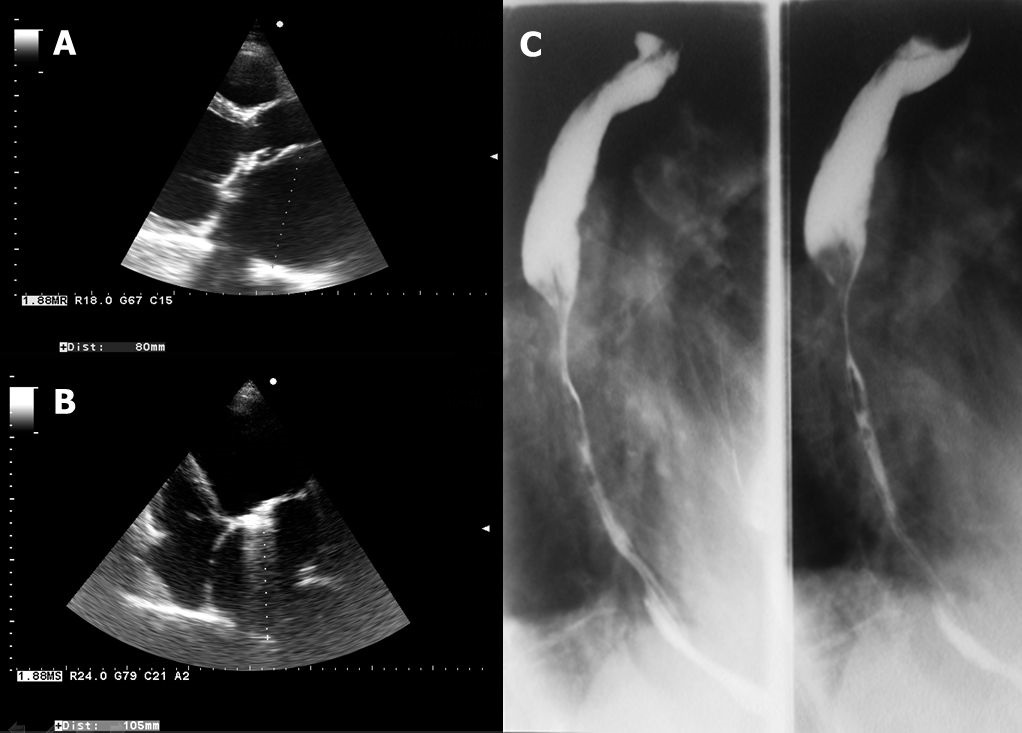

A 65 years old men with mechanical mitral prosthesis (implanted for rheumatic valve disease) was referred to our clinic with signs of advanced heart failure and associated severe dysphagia. This symptom started a couple of years before and became worsened in the last months causing severe difficulties in alimentation, both for solid and liquid foods. Echocardiography revealed a normofunctional mitral prosthesis, a dilated left ventricle with severe systolic dysfunction (EF 15%) and a giant left atrium (A-parasternal long axis view, left atrial postero-anterior diameter = 80mm, B-apical four chamber view, left atrial longitudinal diameter = 105mm). The X-ray examination with barium of the upper gastrointestinal tract demonstrated significant lumen reduction in the middle and lower part of the esophagus (C), corresponding to the external compression caused by the huge left atrium. The explanations for the severely enlarged left atrium would be the late valvular intervention (also suggested by the dilated and dysfunctional left ventricle) and the progression of left atrial remodeling due to chronic inflammation. The patient was referred to esophageal balloon dilation and stent implantation.